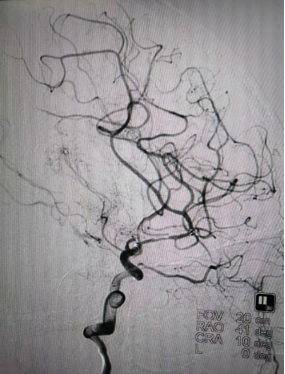

术中造影

DSA(天坛医院-2021.03.17 MCA支架内重度狭窄